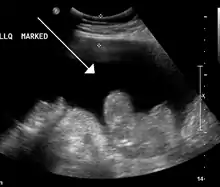

Ultrasound investigation is often performed prior to attempts to remove fluid from the abdomen. This may reveal the size and shape of the abdominal organs, and Doppler studies may show the direction of flow in the portal vein, as well as detecting Budd-Chiari syndrome (thrombosis of the hepatic vein) and portal vein thrombosis. Additionally, the sonographer can make an estimation of the amount of ascitic fluid, and difficult-to-drain ascites may be drained under ultrasound guidance. An abdominal CT scan is a more accurate alternate to reveal abdominal organ structure and morphology.[11]